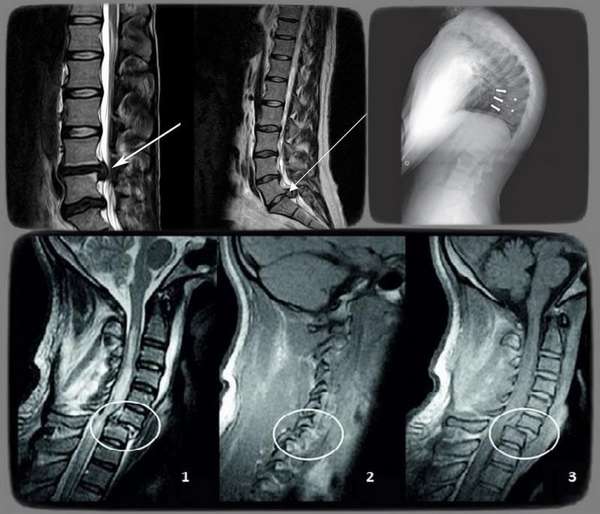

Далее назначаются лабораторные методы (общий анализ крови и мочи) и аппаратные методики исследования (рентгенография, КТ, МРТ).

Справка. Наиболее информативным методом в этом случаев является МРТ, поскольку оно позволяет оценить состояние всех структур, тканей.

Во время данного обследования могут быть выявление такие МР-признаки нарушения статики пояснично-крестцового отдела позвоночника либо другого его сегмента:

- состояние межпозвонковых дисков,

- наличие межпозвонковых грыж,

- степень, направление смещения межпозвонковых дисков,

- аномалии развития позвоночника,

- характер и выраженность искривления позвоночного столба,

- состояние спинного мозга,

- скорость движения и давления спинномозговой жидкости,

- поражение нервной ткани,

- нарушение процесса кровообращения,

- степень патологических изменений костных структур.

Также данная методика позволяет диагностировать травматические, воспалительные, инфекционные, дистрофические процессы в тканях.